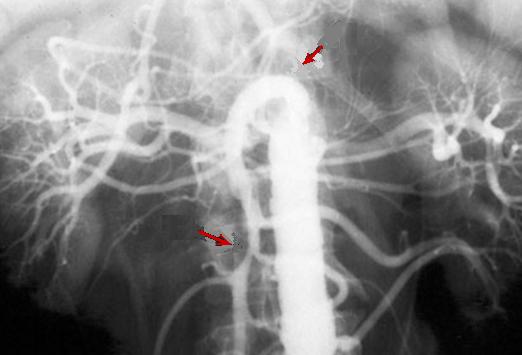

Angiographie

peut etre se presente la occlusion de artere mesenterique

, la diminution de la calibre arterial et dans les thrombose

du veine mesenterique , la veine peut ne se voyait pas mais

elle se represente par des veines collaterales .

| |

Image de occlusion de artere

mesenterique superieure avec de diminution de

calibre arteriale ( fleche rouge ) |

|

Image de thrombose de la

veine mesenteric superieure . Aspect de congestion

une portion de l'intestin |